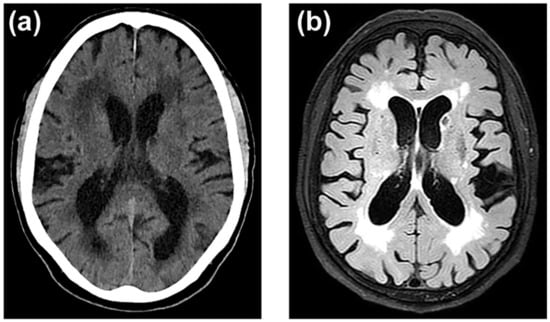

- Hachinski, V.C.; Potter, P.; Merskey, H. Leuko-Araiosis. Arch. Neurol. 1987, 44, 21–23. [Google Scholar] [CrossRef]

- Wardlaw, J.M.; Smith, E.E.; Biessels, G.J.; Cordonnier, C.; Fazekas, F.; Frayne, R.; Lindley, R.I.; O’Brien, J.T.; Barkhof, F.; Benavente, O.R.; et al. Neuroimaging Standards for Research into Small Vessel Disease and Its Contribution to Ageing and Neurodegeneration. Lancet Neurol. 2013, 12, 822–838. [Google Scholar] [CrossRef]

- Ferguson, K.J.; Cvoro, V.; MacLullich, A.M.J.; Shenkin, S.D.; Sandercock, P.A.G.; Sakka, E.; Wardlaw, J.M. Visual Rating Scales of White Matter Hyperintensities and Atrophy: Comparison of Computed Tomography and Magnetic Resonance Imaging. J. Stroke Cerebrovasc. Dis. 2018, 27, 1815–1821. [Google Scholar] [CrossRef]